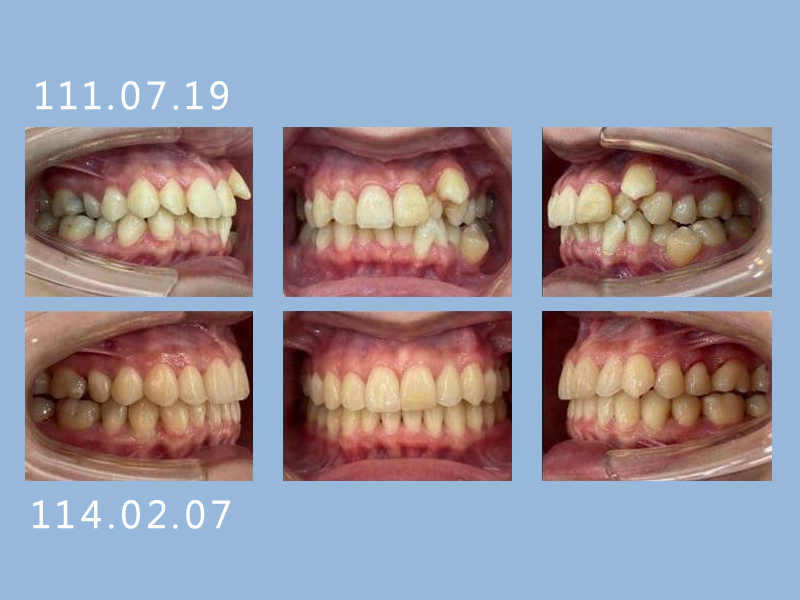

王先生 (22歲) 矯正完成

狀態 : 暴牙、擠、沒拔牙